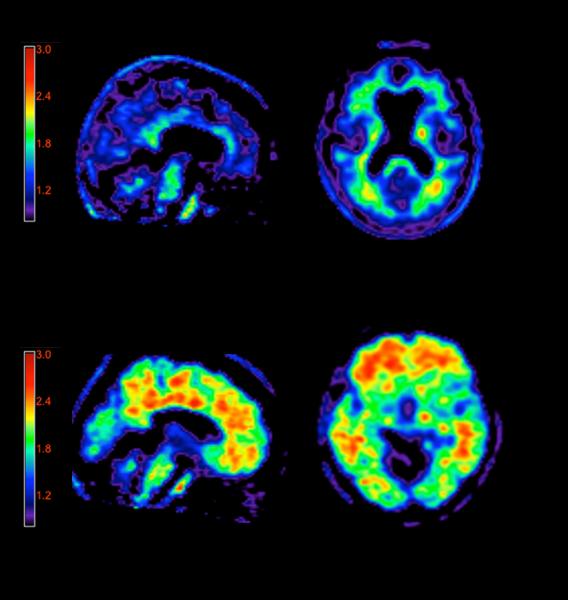

Medical imaging plays an increasing role in the accurate diagnosis and treatment of numerous medical conditions. The ...

Radiation dose management is central to child patient safety. Medical imaging plays an increasing role in the accurate ...